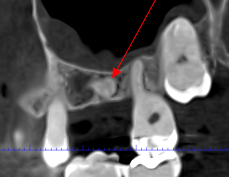

Las extracciones complejas, especialmente de terceros molares inferiores, suponen un reto quirúrgico cuando existe cercanía entre las raíces dentarias y